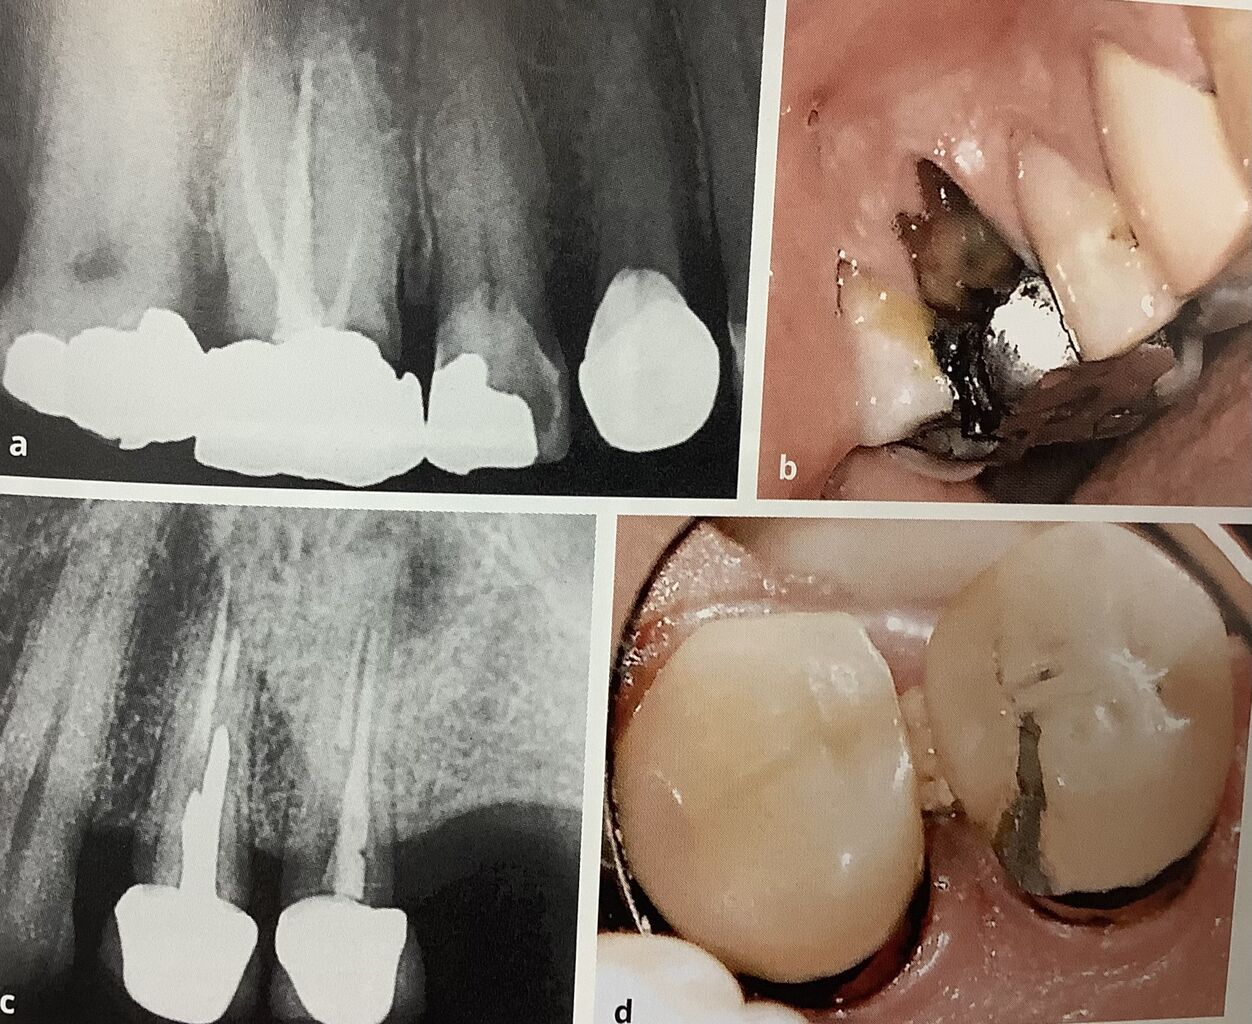

レントゲンで白く見えるのが詰め物や被せ物。

その境目に黒くなっているので、虫歯がまた出来ちゃった。

下の歯ではセラミックが欠けています。

一本には根っこに黒いカゲも見えます。

白いクスリが短くて、根っこにも黒いカゲが。

根元の歯ぐきも腫れています。